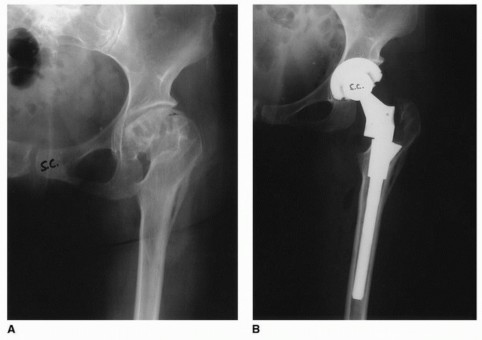

- Developmental Dysplasia of the Hip (DDH): Crowe Type III and IV DDH often present with excessive femoral anteversion, a narrow diaphysis, and a posteriorly displaced greater trochanter. Modular stems allow for distal fixation in the narrow canal and independent retroversion of the proximal body to correct the excessive native anteversion.

Radiographic Evaluation and Templating

Plain radiographs must include an anteroposterior (AP) projection of the pelvis, an AP of the involved hip, and a Lauenstein (frog-leg) lateral x-ray. Radiographic magnification markers (typically a 25 mm or 30 mm sphere) taped to the involved hip at the level of the greater trochanter allow for an accurate estimate of x-ray magnification. This permits precise digital templating of the femoral canal.

Templating a modular stem is a sequential process:

1. Distal Fixation: The distal stem is templated first to ensure adequate cortical contact (typically 4-6 cm of scratch fit in the diaphysis) while bypassing any stress risers or deformity apices by at least two cortical diameters.

2. Proximal Fill: The proximal body is then templated to fill the metaphysis and reconstitute the medial calcar.

3. Offset and Length: The modular neck or proximal body geometry is selected to recreate the center of rotation, horizontal offset, and leg length.

Computer tomography (CT) scans are rarely indicated for routine THA but are invaluable in complex cases to provide a highly accurate assessment of native femoral anteversion, precise femoral canal dimensions, and acetabular bone stock. Scanograms or full-length standing AP radiographs of the lower extremities may be useful to more accurately assess true limb length inequalities and global coronal alignment.